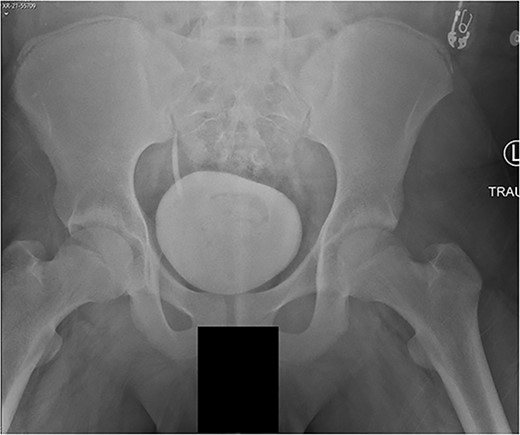

A 14-year-old boy sustained closed right and left mid-shaft femur fractures (Right OTA 32-A3, Left OTA 32-B2) after an all-terrain vehicle accident (Fig. 1a and b). The patient was classified as obese with a BMI of 37. Bone age was determined to be approaching skeletal maturity and so a rigid trochanteric entry femoral rod was selected for the implant [15, 16] (Fig. 2). Laboratory derangement included hyperphosphatemia and hypoalbuminemia. Therefore, additional measures to include early fracture stabilization and the RIA adjunct was selected for our patient [17].

The patient tolerated the procedure well and recovered uneventfully. He was noted to have circumferential osseous healing at 1 year and underwent bilateral femur IMN removal 1.5 years postoperative without complication (Figs 4a–d and 5a–d).

(a) Right femur AP radiograph. (b) Right femur lateral radiograph. (c) Left femur AP radiograph. (d) Left femur lateral radiograph.

(a) Right femur AP radiograph after implant removal. (b) Right femur lateral radiograph after implant removal. (c) Left femur AP radiograph after implant removal. (d) Left femur lateral radiograph after implant removal.